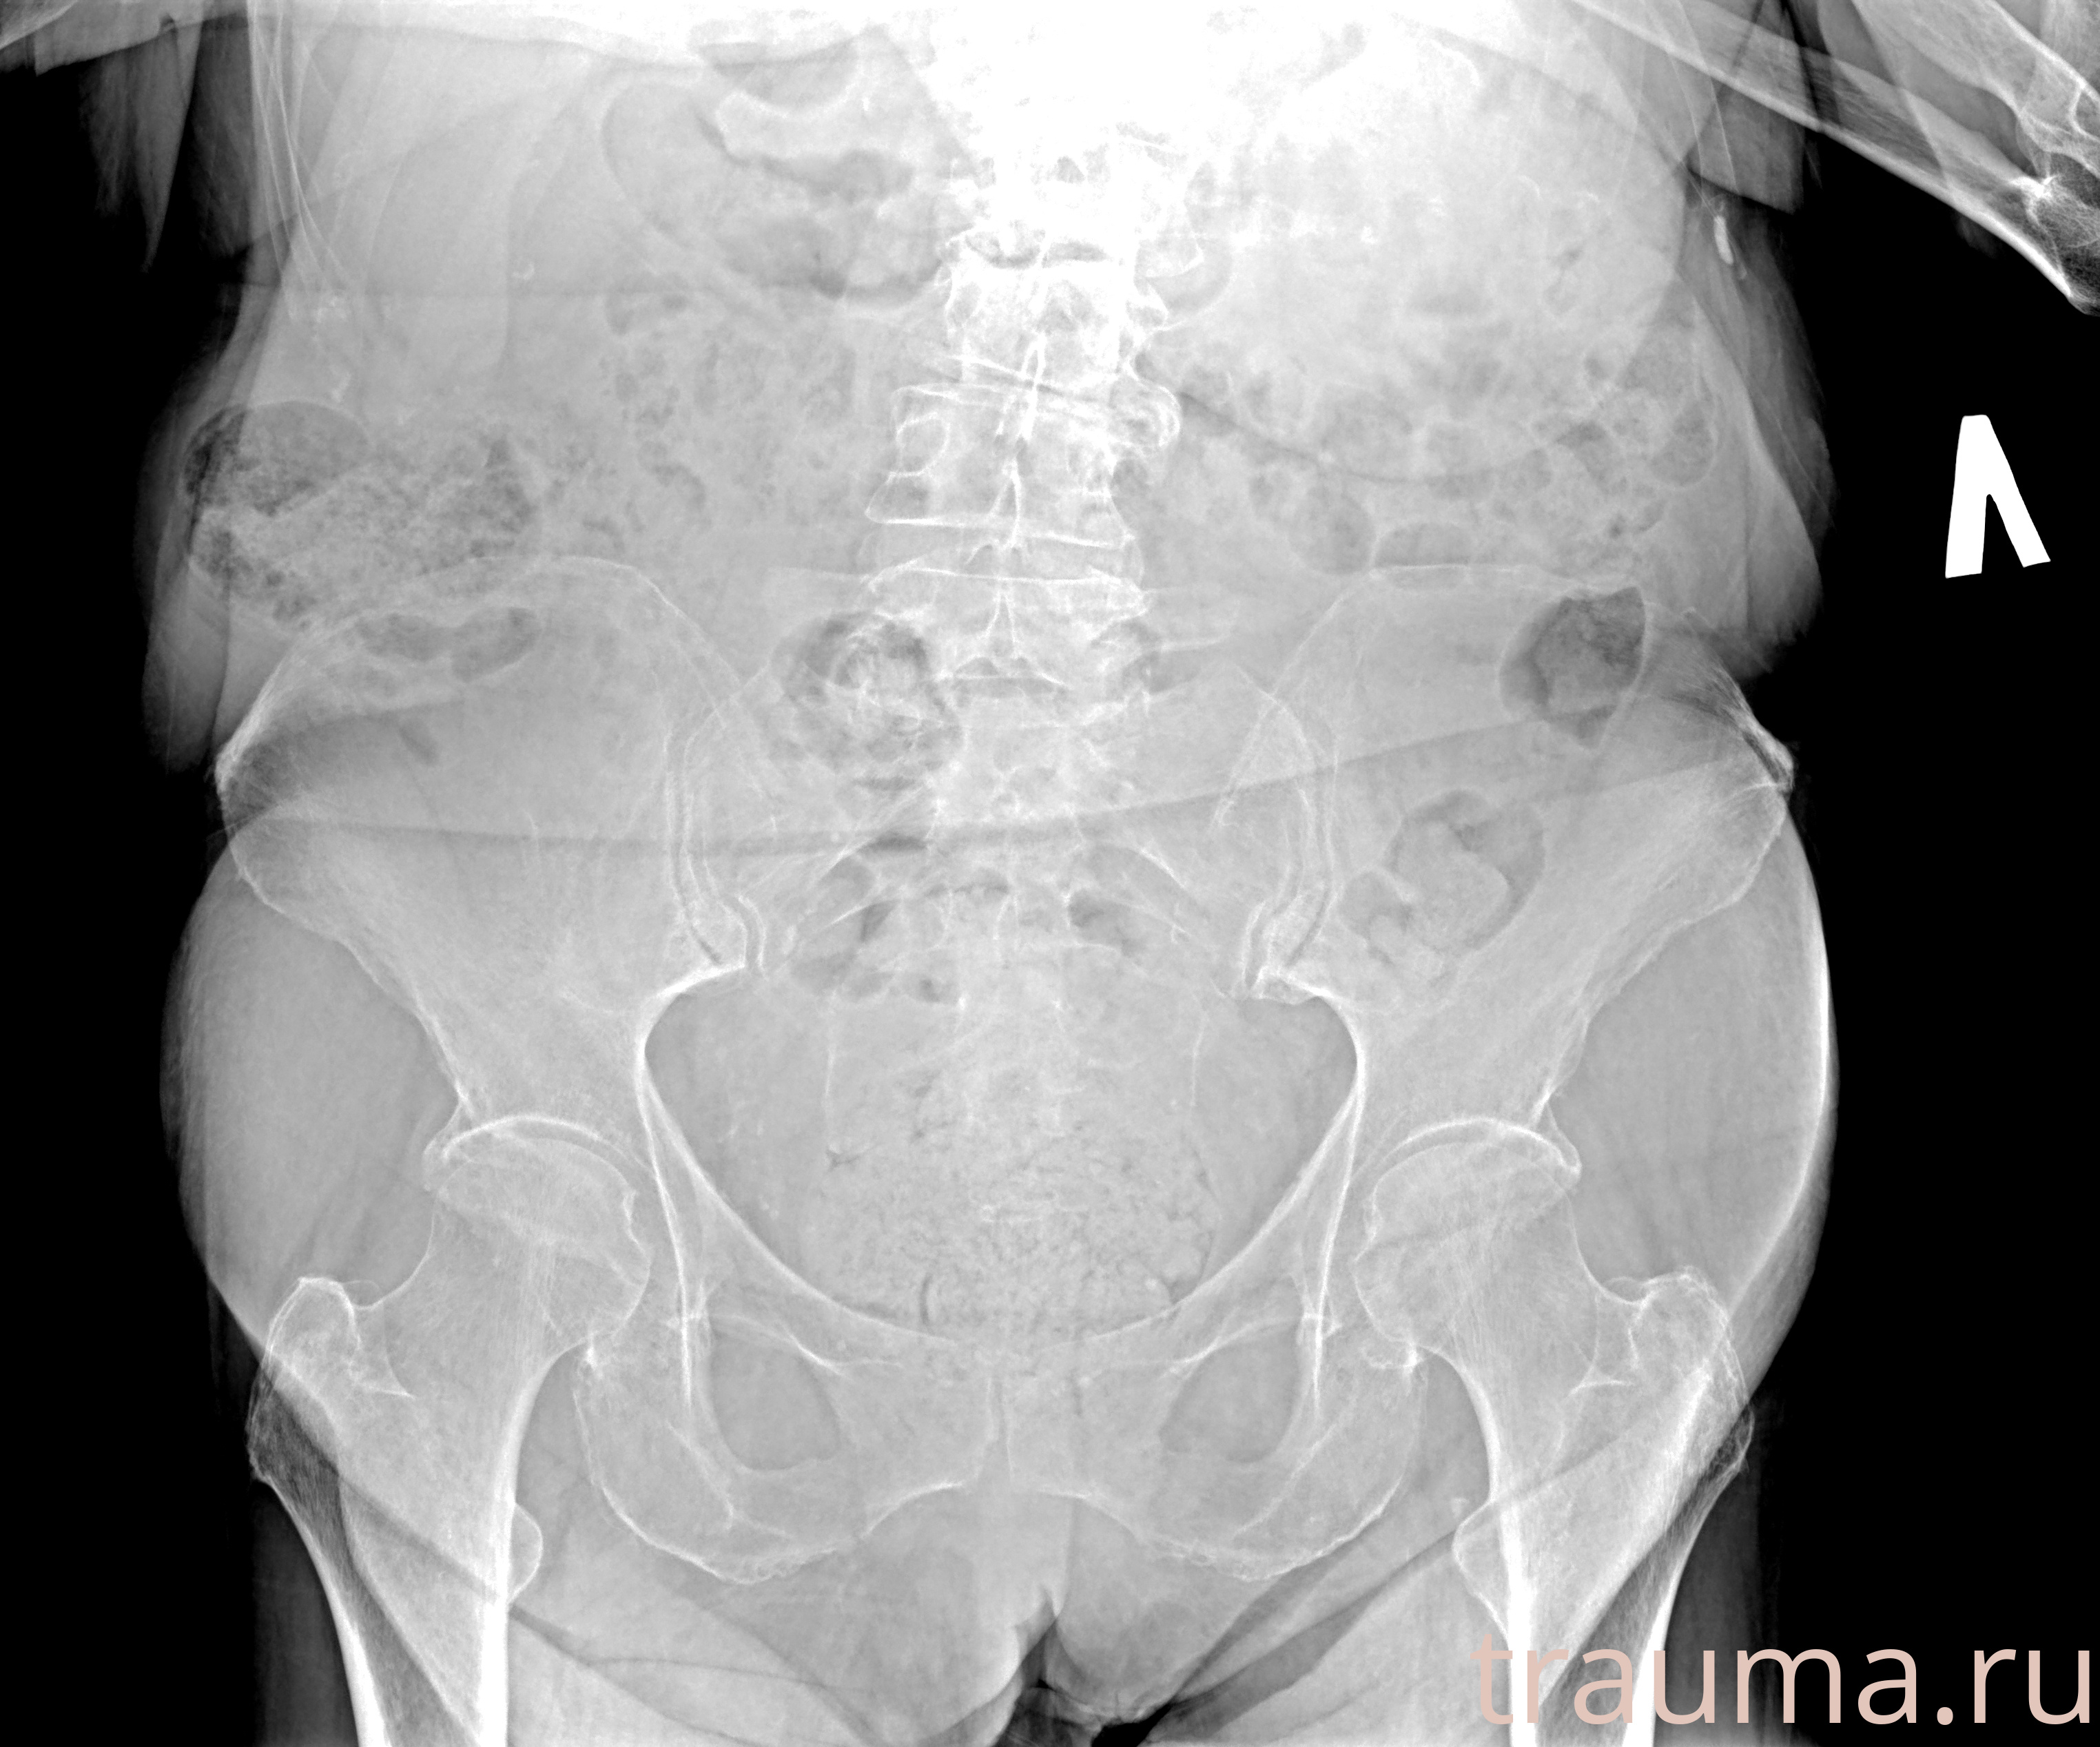

Рентгенограммы

Рентген на дому: по вашему адресу приезжает врач-рентгенолог, травматолог-ортопед с мобильным рентгеновским аппаратом, проводит диагностику травмы или заболевания, делает необходимые рентгенограммы, дает рекомендации по дальнейшему лечению. Получить качественные снимки в домашних условиях возможно благодаря уникальной методике, разработанной МосРентген Центром для института  Склифосовского

при переломе шейки бедра и пневмонии от компании МосРентген Центр - партнера Института имени Склифосовского